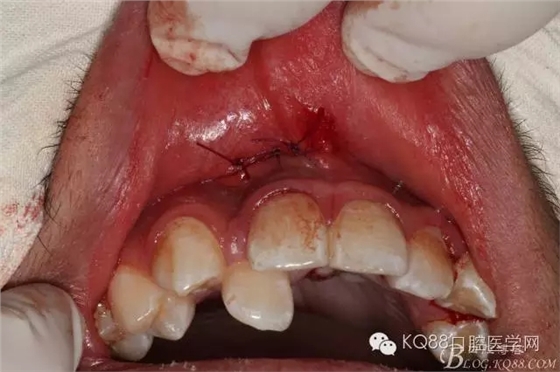

圖15.三針縫合拔牙創(chuàng)口